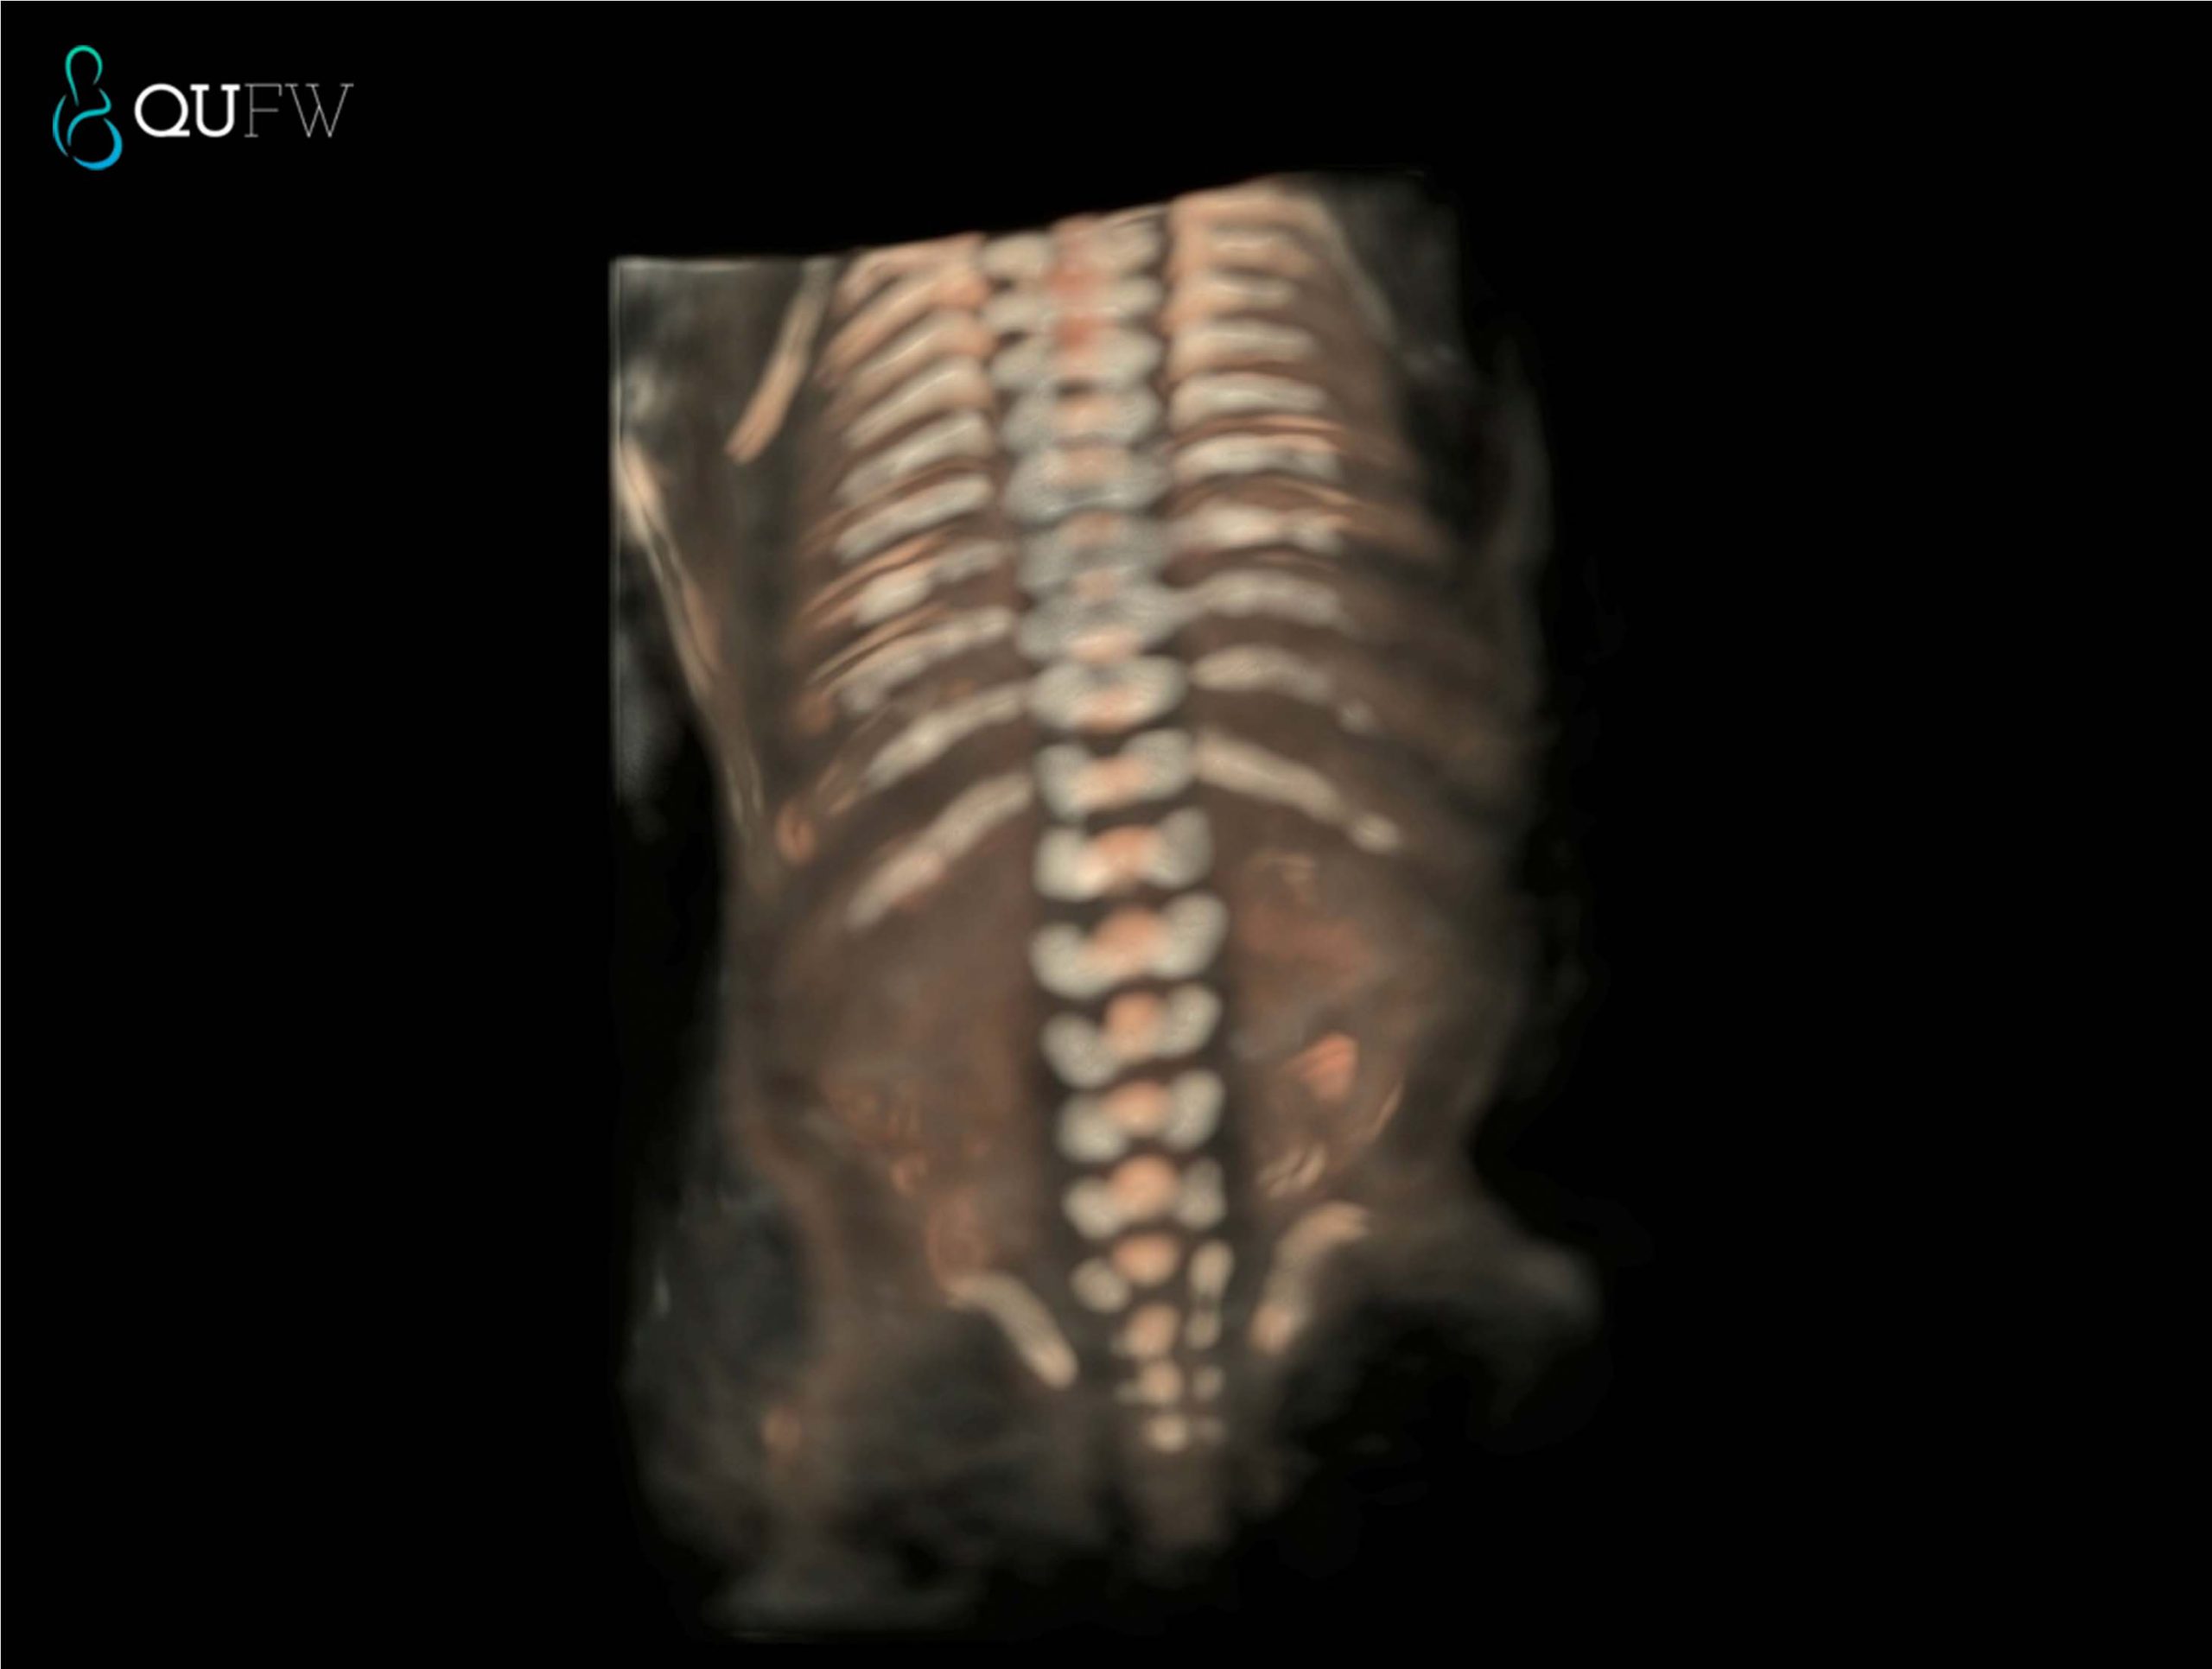

3D/4D Scanning

The majority of the scan is completed in conventional 2D (greyscale) as this offers the best resolution for detecting abnormalities. We will also try to obtain some images in 3D/4D of your baby, but this is very dependent on the baby’s position, the amount of amniotic fluid and maternal issues like placental position and maternal body habitus. The priority of the ultrasound is to check the baby’s well being and to provide you and your doctor with all the information we can in regards to the baby’s health. In reality, it may be difficult to obtain the ‘perfect 3D/4D’ image of your baby due to a variety of reasons. Our staff will make every effort to provide you with some keepsake images.

3D image of a 20-week fetus

3D rendered image of the fetal spine at 20 weeks